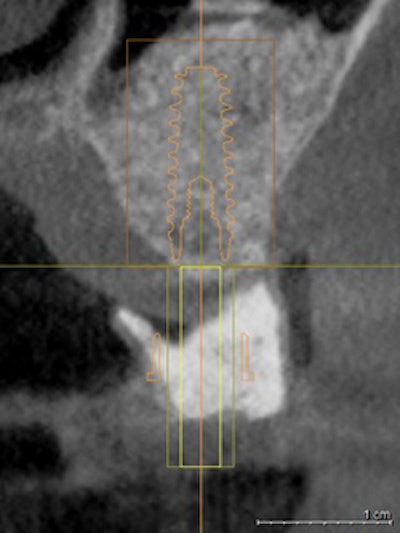

The use of surgical guides (figure 1) is an absolute necessity to place safe, precise, and optimally positioned implants. With the end in mind, I integrate the data derived from my scan and the dental anatomy derived from my Cerec (Sirona) intraoral optical scan to plan and place prosthetically driven implants (figure 2). Multiple benefits follow this protocol, with the most important being positive patient experiences, faster healing, less postoperative discomfort, and little to no interruption of the patient's daily routine.

As you journey into implant placement with surgical guides, your level of confidence rises knowing you will precisely place your implant fixtures based on the 3D virtual plan devised in Galileos implant software. Placing realistic virtual implants into an edentulous site or multiple sites better prepares you for the actual placement (figure 6). I review any of the vital anatomical structures without distortions that might be encountered during surgery and make measurements that can be extremely advantageous when getting close to adjacent teeth, the incisive foramen, the mental foramen, the maxillary sinus, the mandibular canal, or an unusual mandibular concavity, to name a few.

The software provides us with safety margins to avoid penetrating these vital structures. You may find that a crestal sinus lift may be necessary to accept the planned fixture or that decreasing the length of the implant may be appropriate. Either way, you are not blindsided by atypical anatomy or underprepared for your procedure. This goes hand in hand with our "Do no harm" oath.

An additional feature of the Galileos implant software is the implant planning report where you can evaluate various views of the surgical field. Once the surgical guide is sent for fabrication to the SICAT lab in Germany (figure 7) you can be assured that the plan you created will be verified for accuracy and, if there is any problem encountered, a detailed evaluation will follow.

The final acceptance is always up to the clinician, but this is an additional safeguard that ensures the quality of the guide will match the plan and be accurate to submillimetric measurements. You receive the surgical guide, a planning report, and the drilling recipe for each implant planned. This decreases the need for inventory as you can order implants as needed.